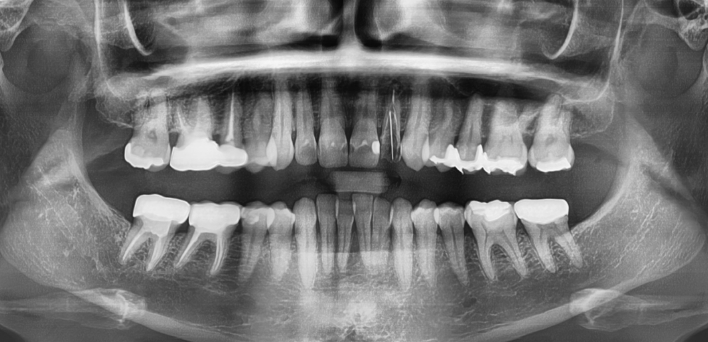

임플란트 : 손 ** 님 (50대)

Before Before

2020.02.30

After After

※ 더서울치과의원은 의료법을 준수하며 위 케이스는 실제 환자의 동의를 얻은 사례로 치료 전, 후가 동일한 환경에서 촬영되었습니다.

환자 케이스에 따라 부작용이 발생할 수 있습니다. 이 부분은 의료진의 충분한 상담과 체크를 통해 예방하고 줄일 수 있습니다.

[임플란트 부작용] 수술 후 관리가 소홀할 경우 출혈, 주위염 등의 부작용이 발생할 수 있어 구강 위생을 철저히 유지하고, 정기적인 검진을 통해 상태를 점검하는 것이 중요합니다.

환자 특징

환자 특징01무치악 상태

환자 특징02수년간 무치악으로 지내심

임플란트가 불가능할것이라

생각하고 내원

위, 아래 6개씩 식립

디지털 풀아치 임플란트

임플란트 Before & After

The seoul dental clinic